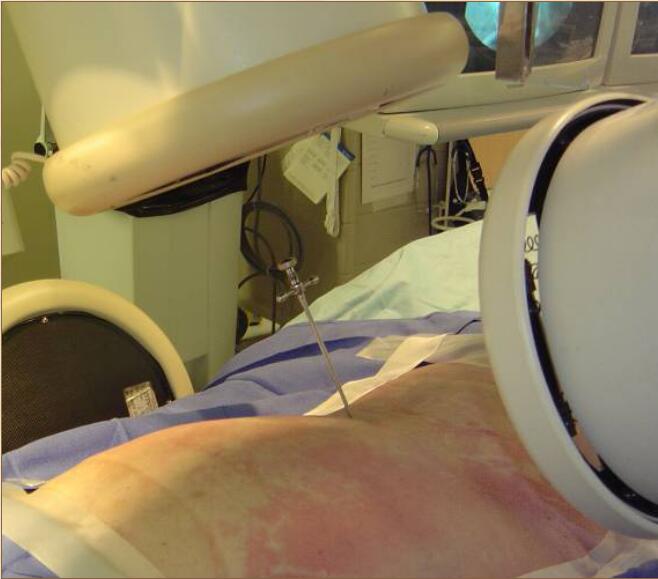

1、插入穿刺針

4、單側(cè)穿刺入路